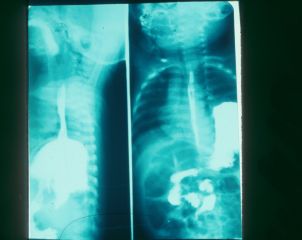

ولولوس معده Gustric Vovolus in Infancy